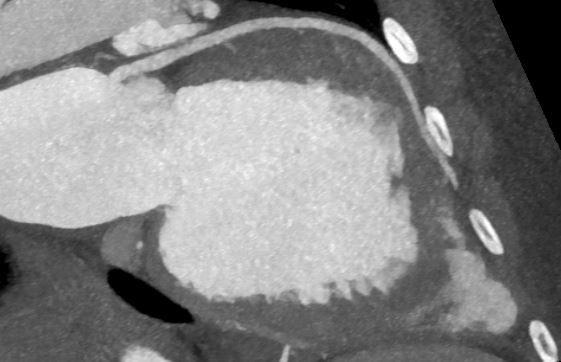

Fig 5: CT: RIVA in close spatial relation to the chest wall